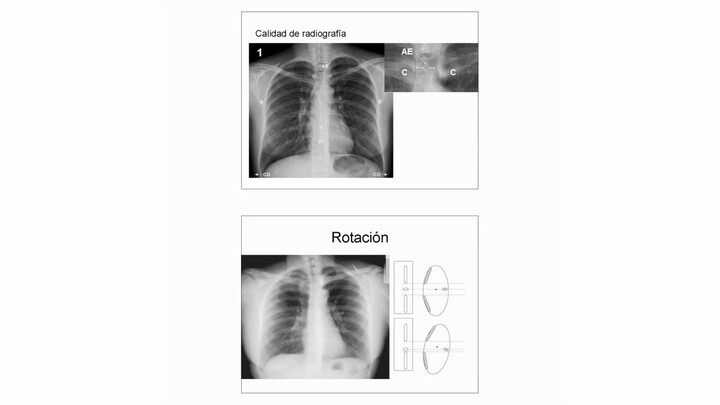

Son bioinfo-presentaciones en credit´s de imagen Flexibilidad (permanencia, resistencia, estabilidad, facilidad o soporte) de diagnóstico que sigue en